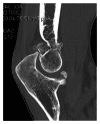

Primary and posttraumatic arthritis of the elbow

Whether degenerative joint disease of the elbow may be the result of primary or posttraumatic etiologies, arthritis of the elbow commonly leads to pain, loss of motion, and functional disability. A detailed history and focused physical examination, in combination with imaging modalities, can help localize the origin of symptoms and help direct treatment. Although nonoperative treatment is the initial therapy for arthritis of the elbow, surgical interventions may provide substantial relief to the appropriately selected patient.